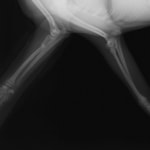

症例3:キルシュナーワイヤーのピンニングによる整復

ペルシャ猫 11ヶ月齢 雄

他院にて左大腿骨遠位の成長板骨折(salter-harrisⅠ型)が認められており、治療相談を目的として来院。当院にて、キルシュナーワイヤーを用いたピンニングにより骨折部位の整復を行いました。術後の経過は良好で、現在も経過観察中です。

術前レントゲン

術後レントゲン